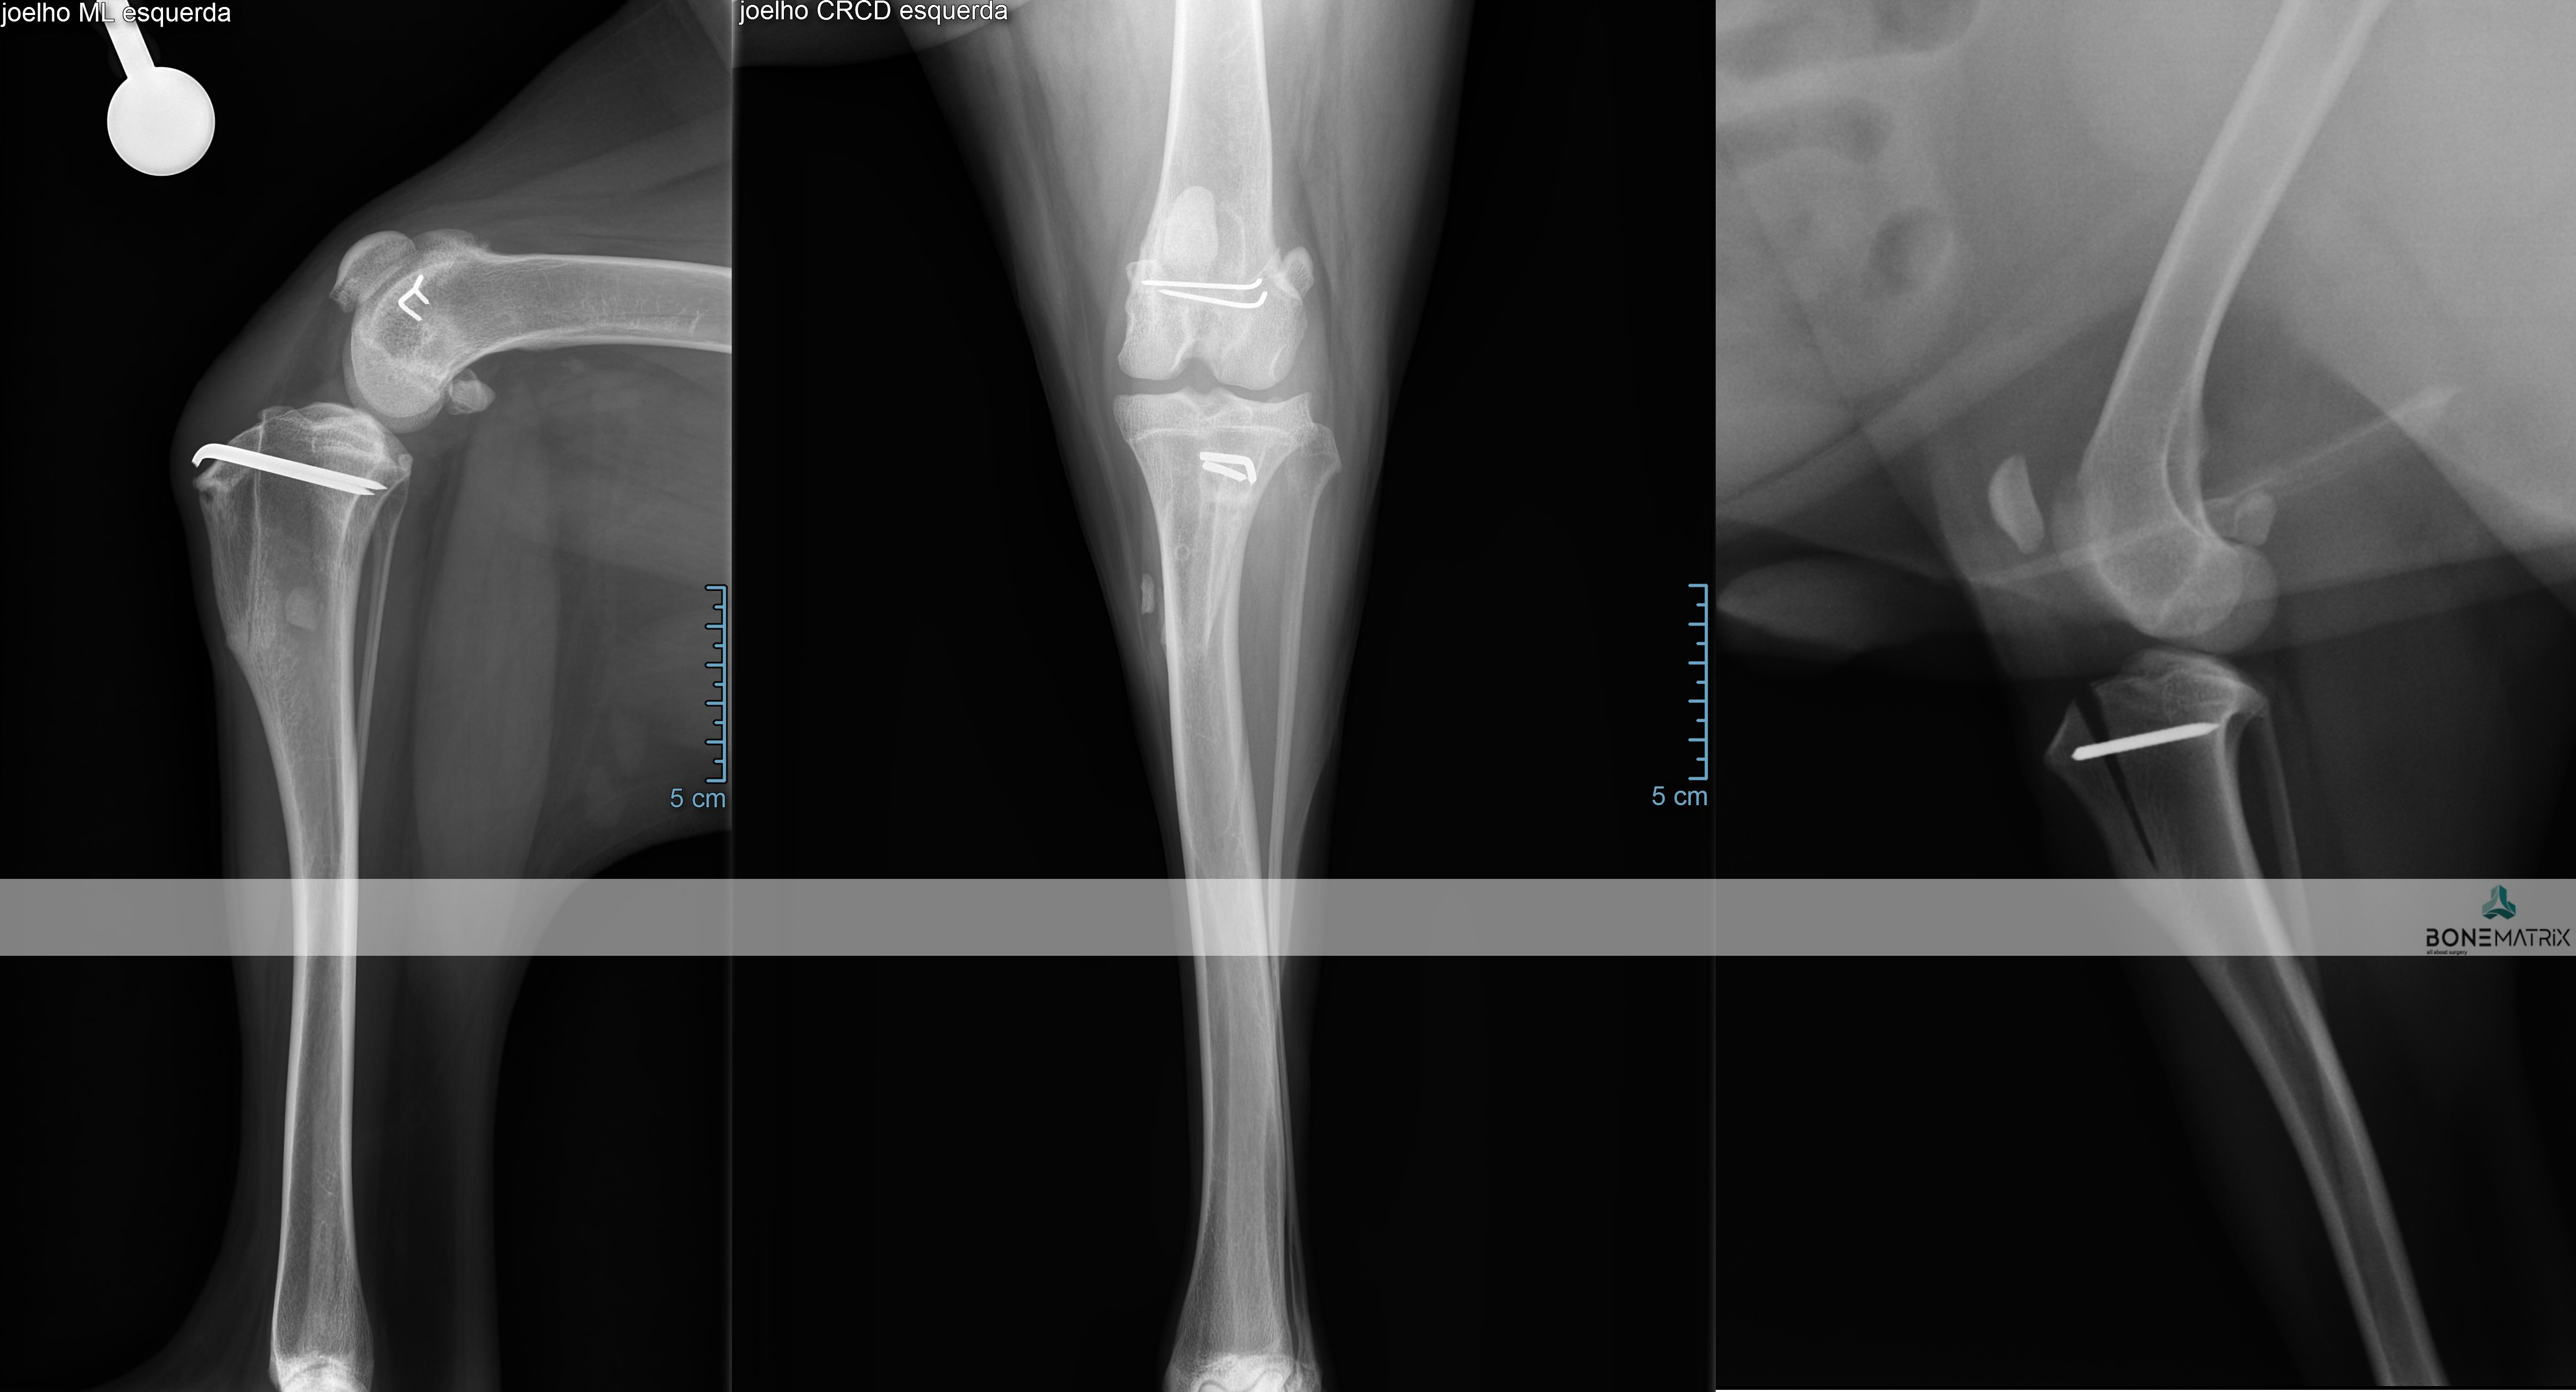

DFO (distal femoral osteotomy) é um procedimento realizado como parte integrante ou abordagem única à patologia de luxação de patela (rótula).

A realização desta cirurgia implica a realização pré-cirúrgica de um planeamento cirúrgico baseado num estudo radiográfico.

No estudo realizado são feitas medições de vários ângulos relacionados com o alinhamento do membro posterior. Estes ângulos influenciam a direção sob a qual é exercida força sobre o joelho, podendo conduzir à luxação de patela.

Caso exista uma deformidade angular no fémur, é aconselhada a correção do ângulo em causa através da técnica DFO, para que a patela consiga permanecer alinhada na sua localização anatómica (sulco troclear).

A técnica consiste na realização de dois cortes no osso, para correção do defeito angular, e posterior estabilização dos cortes feitos com recurso a placas e parafusos bloqueados (implantes com um grau de segurança superior).

PTO (proximal tibial osteotomy) é um procedimento cirúrgico utilizado para correção de deformidades angulares presentes na tíbia.

A realização deste procedimento exige um estudo radiográfico com planeamento cirúrgico anterior ao procedimento cirúrgico. Neste são medidos ângulos relacionados com o alinhamento do membro posterior.

A cirurgia consiste na realização de dois cortes, previamente planeados, na tíbia, seguindo-se a sua estabilização por meio de placa e parafusos bloqueados (estes implantes apresentam um alto grau de segurança na sua utilização).

Dada a versatilidade desta técnica, várias patologias podem ser corrigidas com esta abordagem, nomeadamente luxações de patela e outras deformidades do membro posterior.

Nesta cirurgia também são utilizadas com frequência guias 3D que definem o local de corte com elevada precisão. Estas guias são planeadas a partir de imagem de TAC em softwares de especialidade e seguidamente são produzidas no nosso laboratório 3D, de forma a estarem adaptadas as características individuais de cada paciente.

A TTT (tibial tuberosity transposition) é uma técnica cirúrgica que pode ser utilizada como componente única ou integrada nos procedimentos necessários para a correção de luxação de patela.

A TTT consiste na realização de um corte ao nível da tíbia que altera a posição do tendão patelar (inserido na tuberosidade tibial).

Ao movimentar esta estrutura vamos alterar o angulo de inserção do tendão patelar e movimentar por consequência a patela (rótula) para a sua posição anatómica (dentro do sulco troclear).

A nova posição que pretendemos que seja assumida pela tuberosidade tibial é fixada por meio de um K-wire (implante cirúrgico).